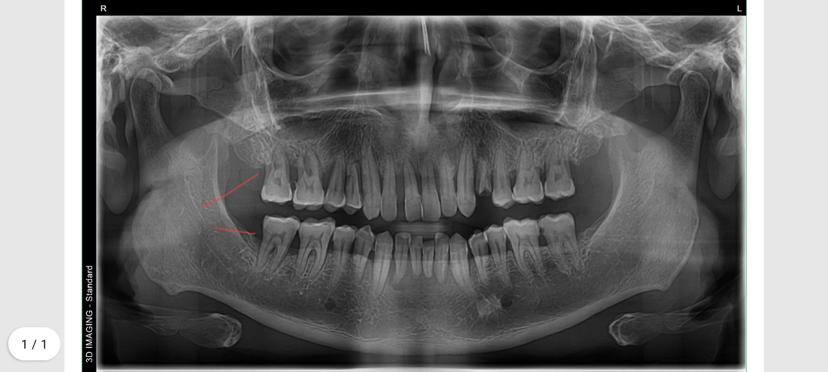

Impacted Teeth